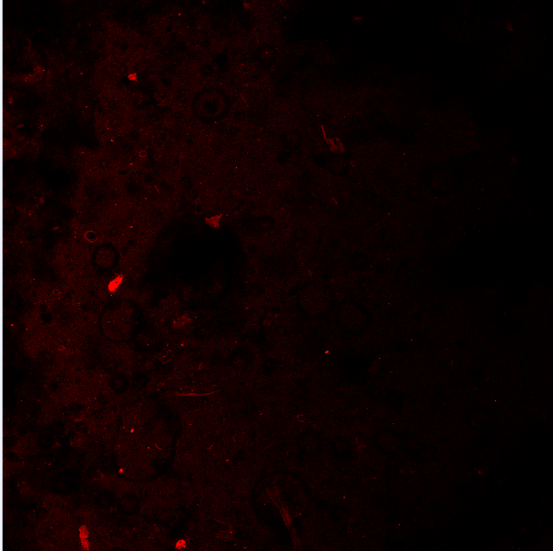

Ó«¹âÔλÔÓ½»£¨FISH£©Í¼Æ¬ÎÊÌâ ÒÑÓÐ1È˲ÎÓë

ÄãÅĵ½µÄÓ¦¸Ã²»ÊǾú£¬ÊÇÔÓÖÊ ·¢×ÔСľ³æIOS¿Í»§¶Ë |

°¡£¿ÔÓÖʶ¼ÕâôÁÁ°¡£¿Ö®Ç°ÎÒʦÐÖ×öµÄÒ²ÊÇÕâÑù£¬ÊÇÎÒÃÇûÔÓ½»ÉÏ£¬»¹ÊÇÎÒÃÇÕÒµÄÊÓÒ°²»¶Ô°¡£¿ ·¢×ÔСľ³æAndroid¿Í»§¶Ë |